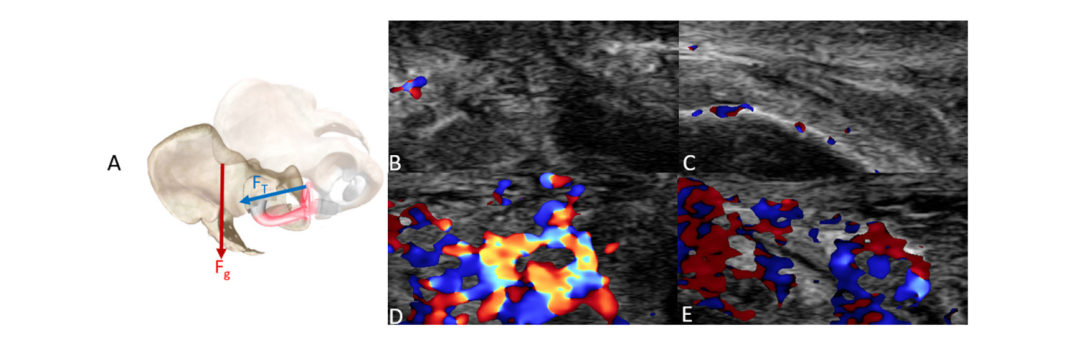

在面对面-男上位的姿势下,使用枕头和不使用枕头对比:效果有明显差异!

▲面对面-男上位不使用枕头